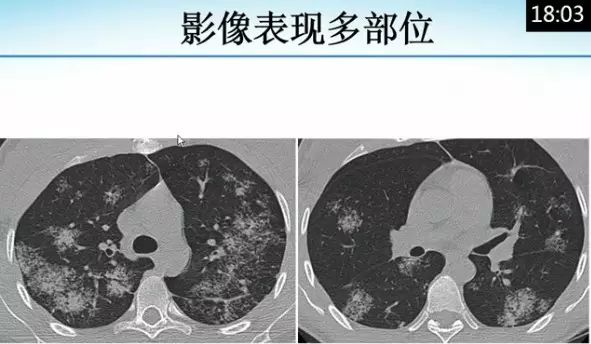

肺内“烟花征”,为活动性肺结核的CT表现之一。是结核经支气管播散并由多发小叶中央结节堆积而成,形态特征似烟花在空中散开。病理基础为细支气管及肺泡内干酪坏死性肉芽肿。

下文为解放军总医院放射诊断科赵绍宏教授课件分享,希望同行朋友们下次遇到类似病例,能够正确诊断。再次感谢赵教授的精彩讲解。